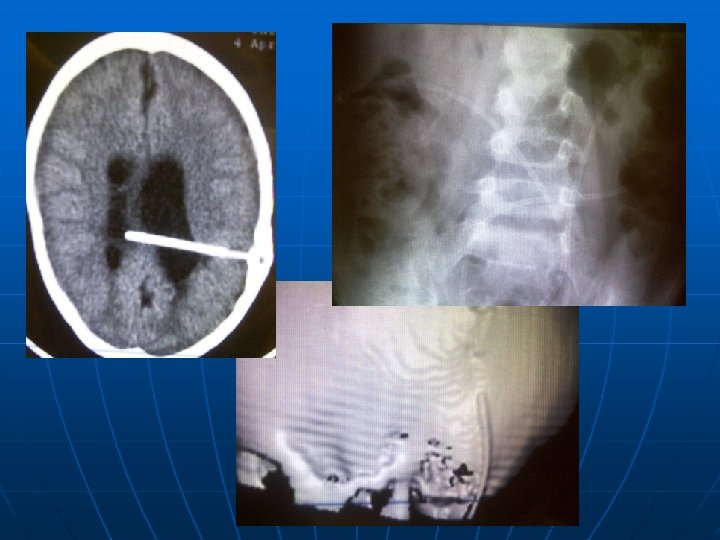

При поступлении больных с признаками дисфункции ликворошунтирующей системы проводится стандартное дообследование в экстренном порядке: -КТ головного мозга, -шунтография, -УЗИ брюшной полости (наличие свободной жидкости), -пункция клапана с исследованием ликвора

Осложнение при замене вентрикулярного катетера: повреждение сосудистого сплетения, ВЖК

Кровотечение, пневмоцефалия после ревизии вентрикулярного катетера